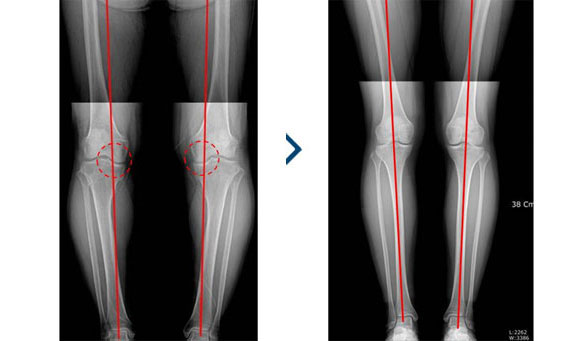

‘O’자형 휜다리를 곧게 교정해

퇴행성 관절염 치료, 만족도 높아

퇴행성 관절염이 악화되어 O 자형 다리로 변형되었을 경우 이러한 휜 다리를 바르게 고정하여 무릎 안쪽으로 집중되어 있는 무게를 외측으로 분산시켜 통증을 감소시키고 무릎의 뼈를 교정하는 수술방법입니다.

일반적으로 보행 시 무릎은 안쪽으로만 힘을 받게 됩니다. 이런 이유로 퇴행성 관절염은 안쪽부터 진행이 되며 특히 O자형 다리가 있는 경우 안쪽에서 부하되는 체중이 더 크기 때문에 관절염이 빠르게 진행됩니다. 안쪽에 연골이 닳으면 내측 간격이 적어지면서 오히려 O자형 다리가 심해지는데, 이렇게 내측 관절염에 영향을 미치는 O자형 다리를 교정하기 위하여 이 같은 수술을 진행하게 됩니다.

O자 다리를 바로 잡아 주어 미용적으로도

만족할 수 있습니다.